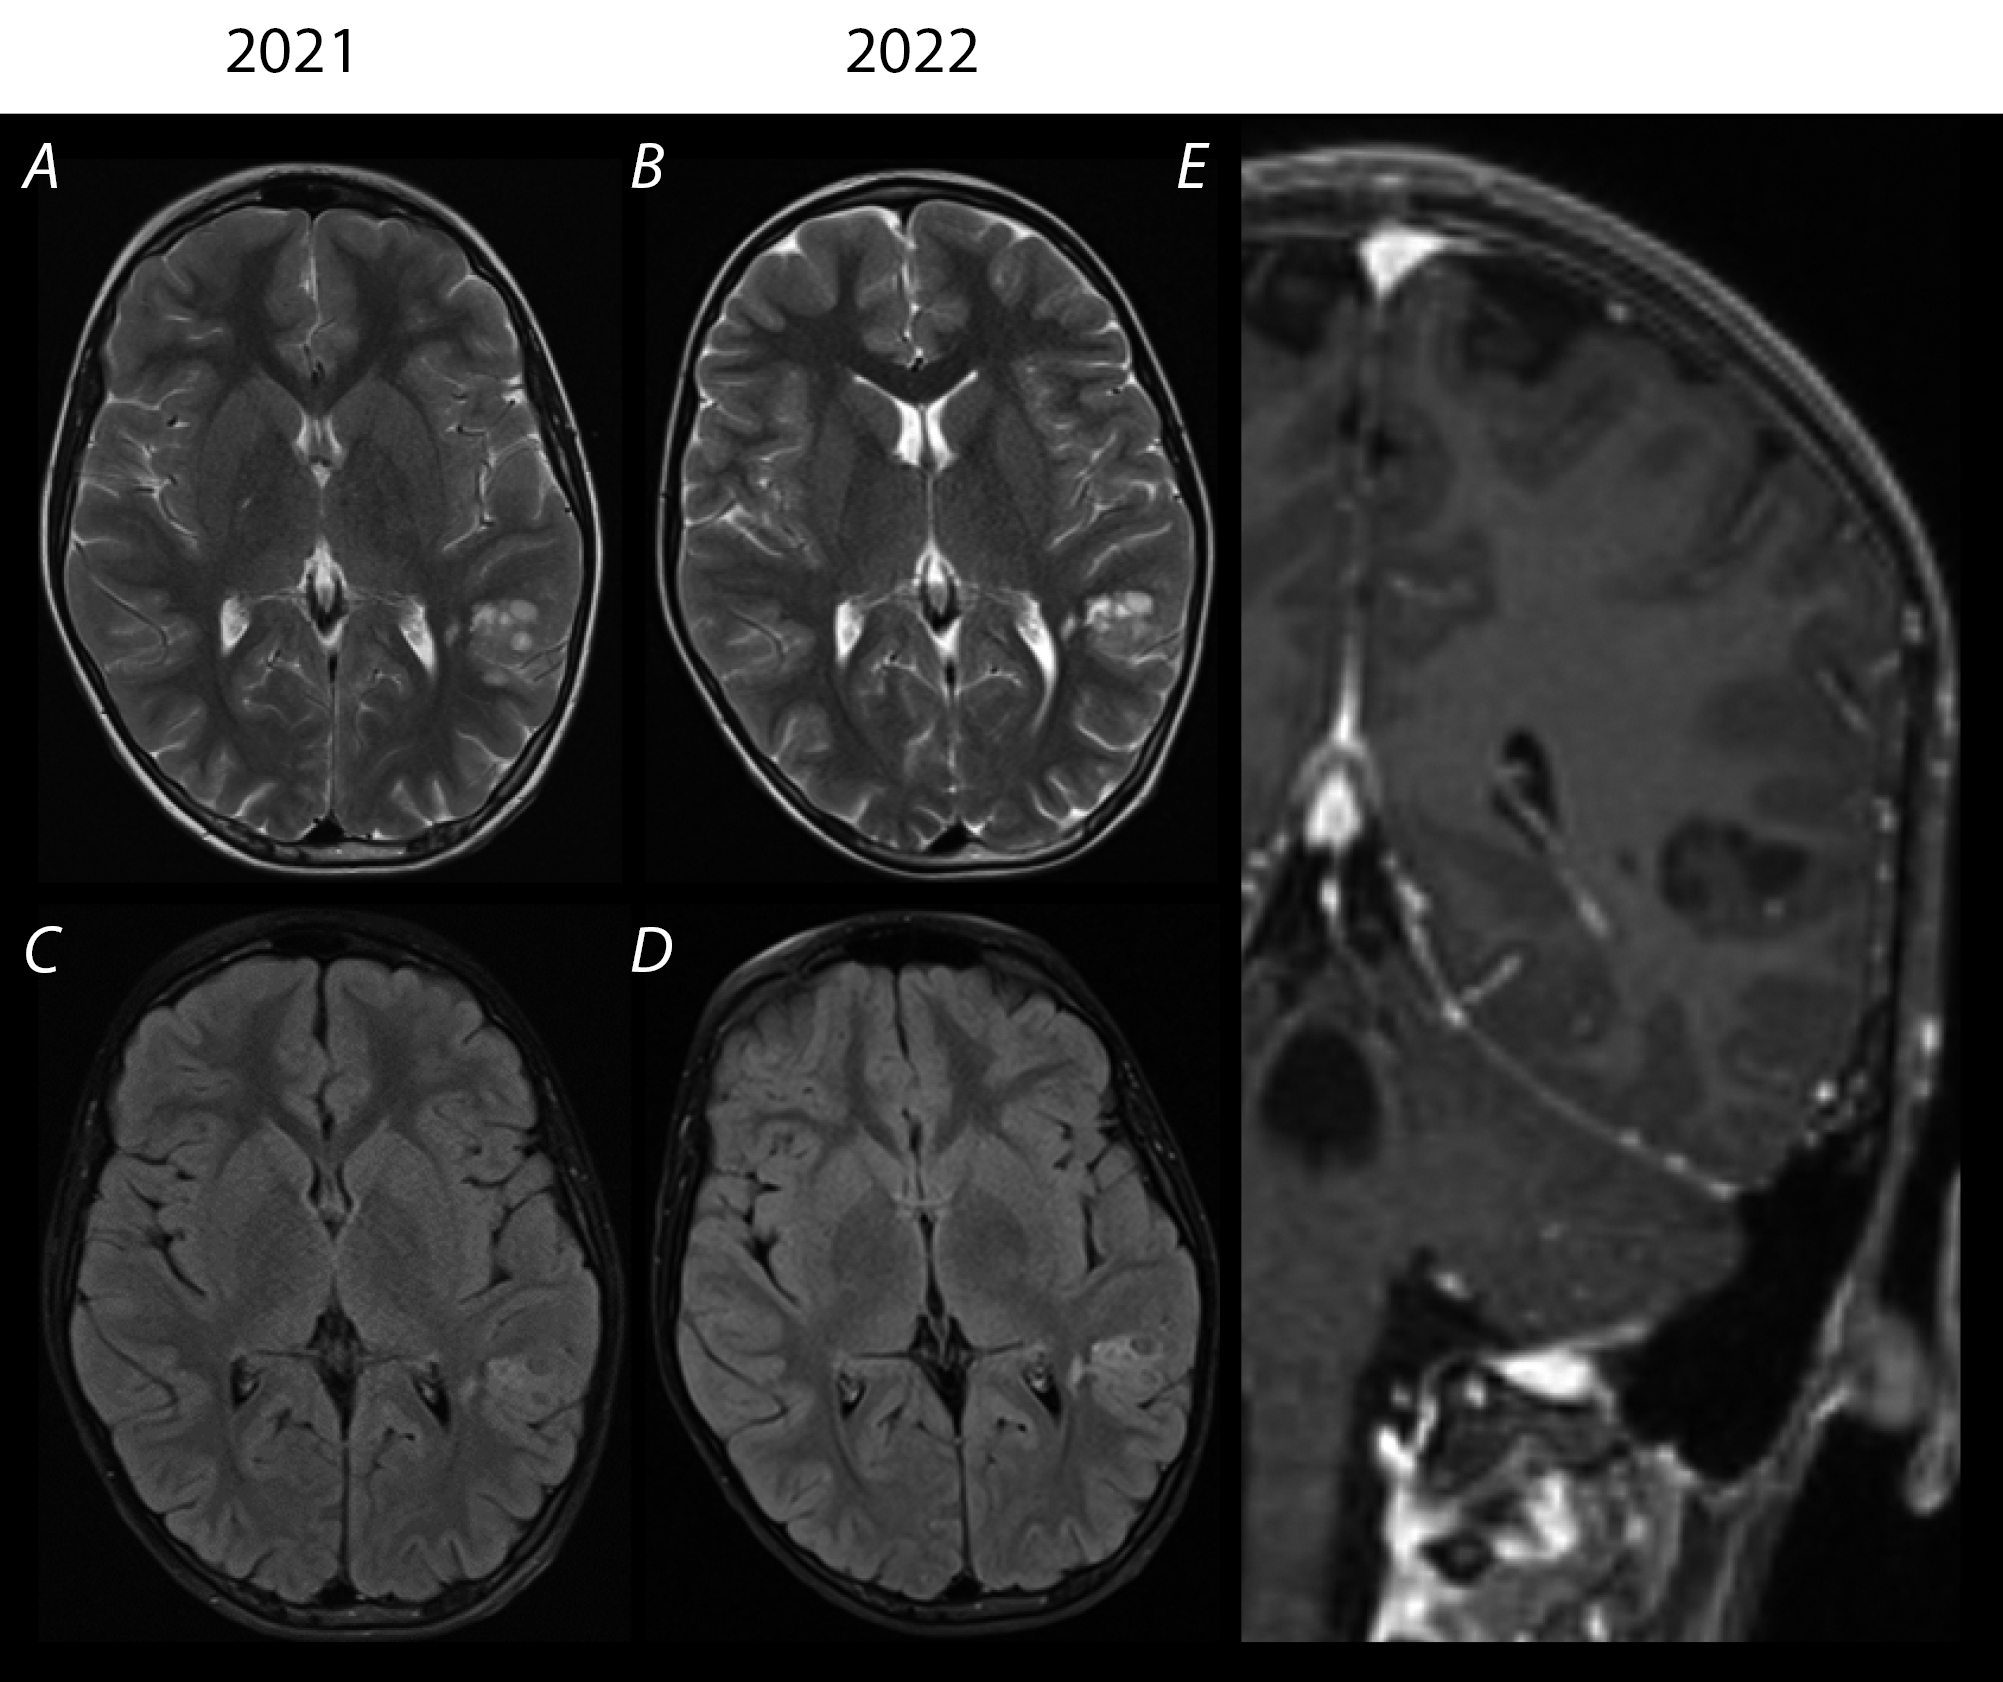

Рис. 2. Динамические МРТ головного мозга пациента Г. через 1 год.

При анализе изображений от 2021 и 2022 гг. определяются более высокие релаксационные характеристики образования в импульсных последовательностях Т2 и FLAIR. Более отчётливая визуализация мультикистозной структуры и трансмантийного распространения в область заднего рога левого бокового желудочка. При ретроспективном сравнении явных признаков прогрессии размеров, присоединения перифокальной реакции и масс-эффекта не отмечается (А–D). При внутривенном введении магнитно-резонансного контрастного средства патологической аккумуляции контрастного вещества в структуре патологического субстрата не выявлено (E).

Fig. 2. Follow-up brain MRIs of patient G. 1 year later.

When images from 2021 and 2022 are compared, higher relaxation properties of the lesion are determined in the T2 and FLAIR MRI sequences. The multicystic structure and transmantle spread to the posterior horn of the left lateral ventricle are visualized more clearly. The retrospective comparison shows no signs of enlargement, perifocal reaction, or mass effect (А to D). No abnormal accumulation of an intravenous MRI contrast agent is seen in the structure of the lesion (E).